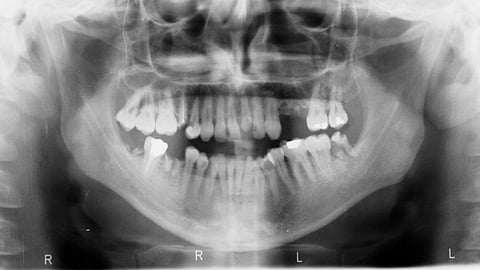

Problems with the third molar have become increasingly common because:

Earlier, our ancestors consumed raw food, which resulted in larger jaw sizes that could accommodate third molars without causing significant issues. However, due to the modern consumption of processed food, the efficiency of chewing hard and raw food has decreased. This has led to reduced and insufficient development of the retromolar space needed for normal tooth eruption. As a result, the impaction of third molars has become more common. (1)

What are the indications for the removal of third molar: